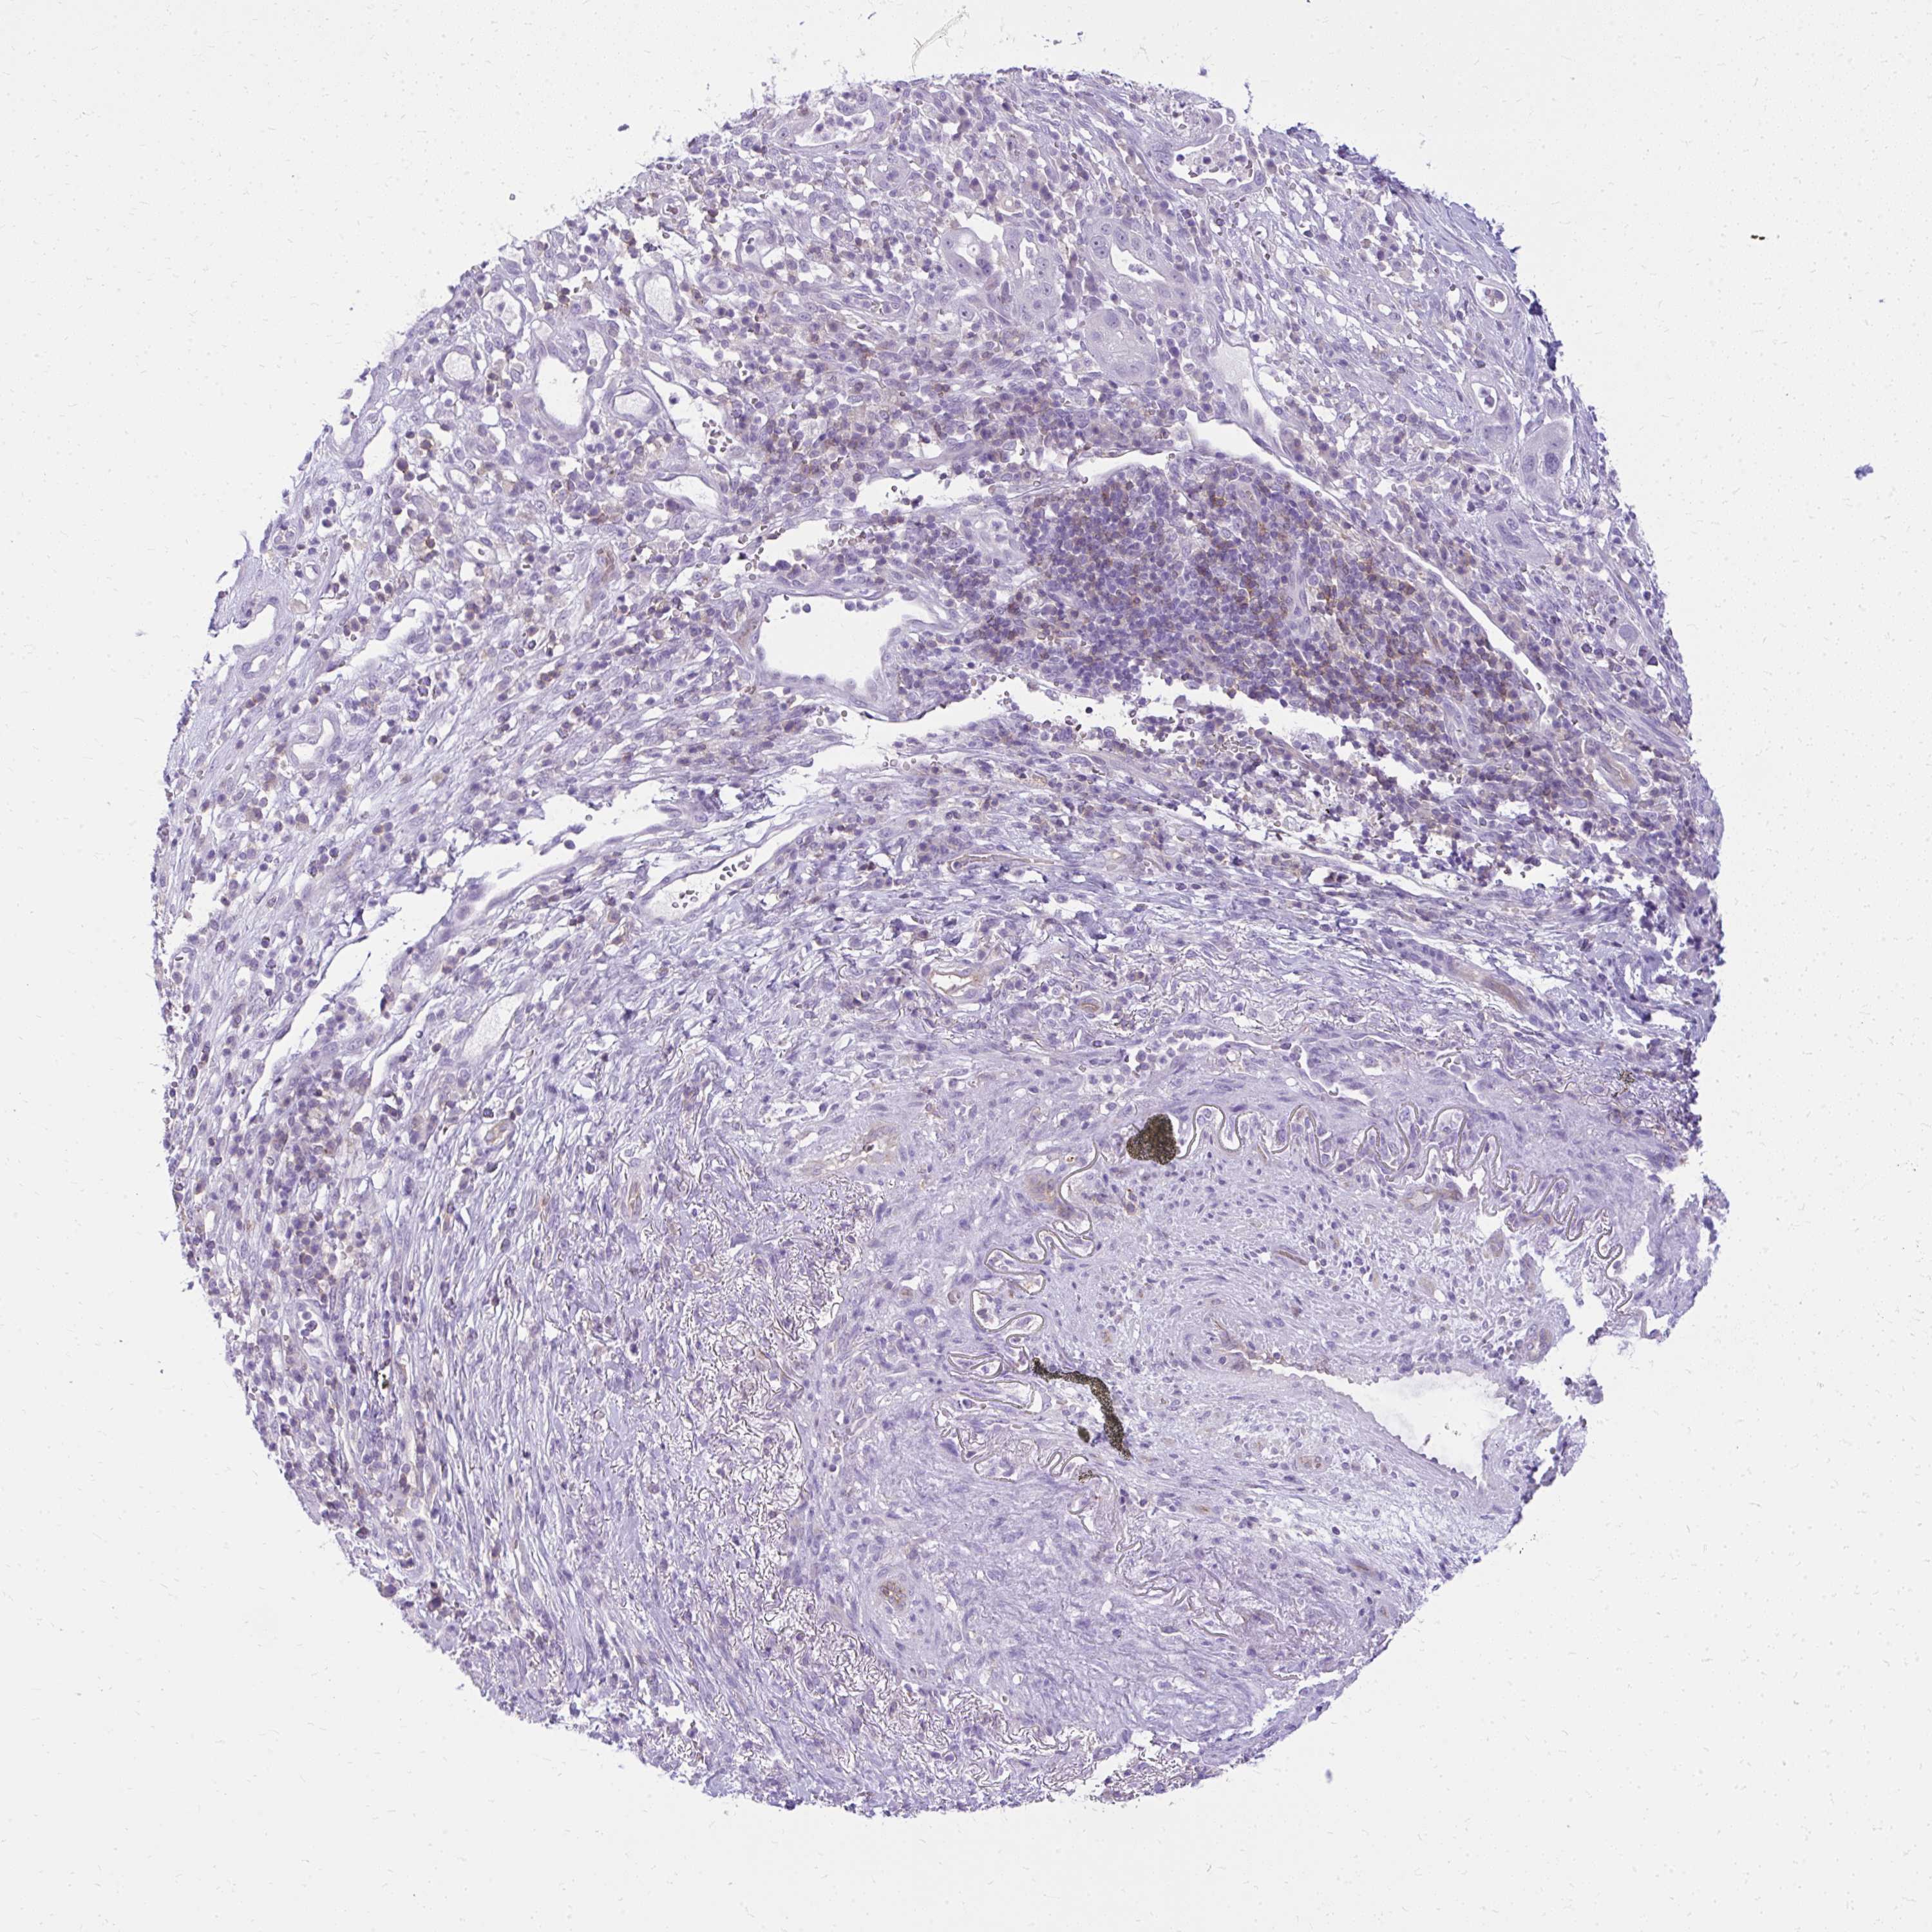

PANCREATIC CANCER - Protein expressioni

A mouse-over function shows sample information and annotation data. Click on an image to view it in a full screen mode. Samples can be filtered based on level of antibody staining by selecting one or several of the following categories: high, medium, low and not detected. The assay and annotation is described here.

Note that samples used for immunohistochemistry by the Human Protein Atlas do not correspond to samples in the TCGA dataset.

Antibody stainingi

Antibody staining in the annotated cell types in the current human tissue is reported as not detected, low, medium, or high, based on conventional immunohistochemistry profiling in selected tissues. This score is based on the combination of the staining intensity and fraction of stained cells.

Each image is clickable and will lead to virtual microscopy that enables deeper exploration of all samples and also displays staining intensity scores, fraction scores and subcellular localization as well as patient and tissue information for each sample.

Antibody HPA057666

Antibody HPA059092

Adenocarcinoma, NOS